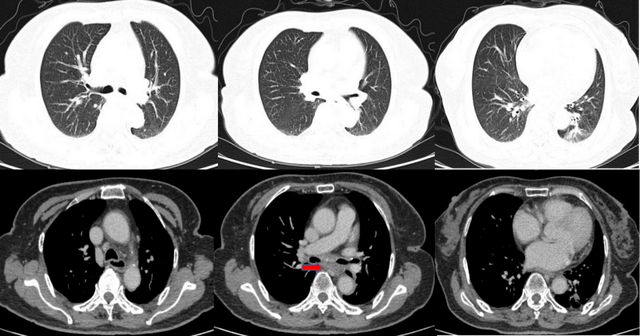

2021年3月1日疗效评估为疾病稳定(SD),2021年11月10日疗效评估为PR;2022年4月18日,用药约14个月时,疗效评估为PD,再次表现为7组纵隔淋巴结增大。之后建议患者采用原方案+局部放疗,但患者选择原方案继续服用2个月(未放疗)。

图4. 2021年3月1日胸部CT复查结果(疗效评估为SD)

图5. 2021年11月10日胸部CT复查结果(疗效评估为PR)

图6. 2022年4月18日胸部CT复查结果(疗效评估为PD)